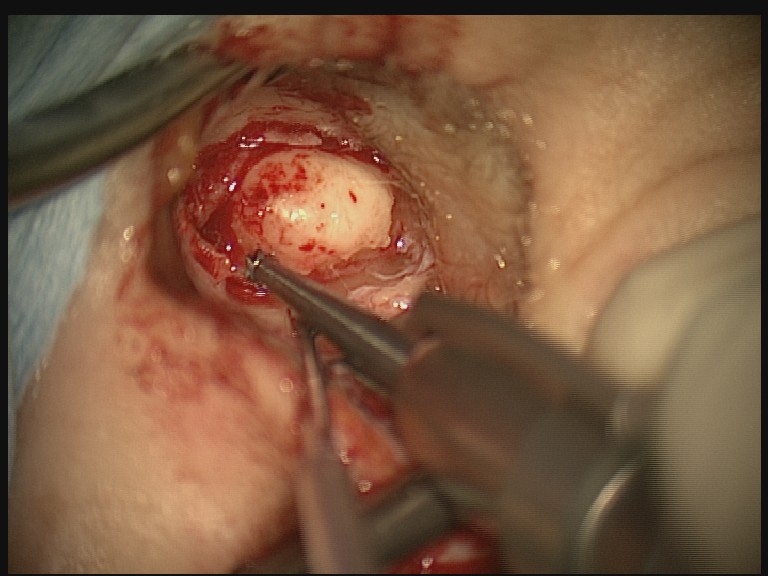

This piece of bone is an exostosis and was chiseled off an ear canal. The exostosis grow in particular layered way that enable them to be effectively removed using a chisel (shown next to the bone).

There are two techniques surgeons use for removing the bone: drilling and/or chiseling. You are put to sleep with a general anaesthetic for the operation.

A cut is made just in front or behind the ear. The skin of the ear canal that’s overlying the bony growths is then lifted up as a skin flap. This skin flap is kept intact so that it can be replaced at the end of the operation to reline the ear canal.

Using a chisel to remove the bone has become more popular particularly in the UK and US over the last decade. Chiseling takes advantage of the way these exostosis grow. They consist of horizontal flat layers of bone cells. The chisel is used to gently fracture along these natural planes of cleavage (weak points in the bone). A bit like how you would use an axe to split wood. But with a lot more finesse! This technique makes it much easier to preserve the ear canal skin in a healthy state and the ear canal heals quickly after the operation. Surgeons who prefer the drill would however argue that the chisel is unsafe as it could create a fracture into the delicate structures in the middle ear.